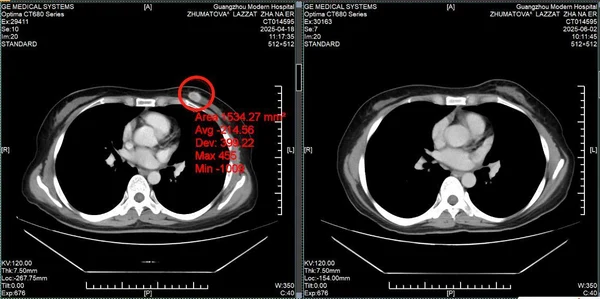

История пациента: Ляззат, 47 лет, юрист, Казахстан. Диагноз: Рак молочной железы IV стадии с множественными метастазами в печень. Тактика лечения: Комбинация интервенционной терапии (химиоэмболизация) и микроволновой абляции (МВА). Результат: Полная регрессия опухоли в молочной железе, уменьшение метастазов в печени более чем вдвое, нормализация функции печени и онкомаркеров. Неожиданная находка: когда привычный мир рухнул Ляззат - успешная женщина из Казахстана, юрист, привыкшая решать сложные задачи в суде, в начале 2025 года столкнулась с самым тяжелым делом в своей жизни. Обследование, начатое из-за усталости и скачков давления, привело к шокирующему открытию: во время УЗИ случайно обнаружили опухоль в печени, а вскоре она сама нащупала уплотнение в груди. Диагноз прозвучал как приговор: рак молочной железы IV стадии с множественными метастазами в печень. Местные врачи настаивали на единственном, по их мнению, варианте: длительном курсе химиотерапии и обязательной мастэктомии - удалении молочной железы. Принципиальное решение: сохранить не только жизнь, но и себя Для сильной и осознанной женщины это было неприемлемо. «Грудь - это не просто орган, это часть моей женской идентичности. Я никогда не соглашусь на ее удаление и должна найти лучшее решение», - так Ляззат сформулировала свою позицию. Она обратилась в клиники Турции, Индии, Южной Кореи, но нигде не получала гарантий, что лечение сможет победить рак и сохранить грудь. В момент отчаяния надежду подарила подруга, порекомендовавшая St.Stamford Modern Cancer Hospital Guangzhou и его малоинвазивные подходы.

После онлайн-консультации с врачами из Гуанчжоу Ляззат обрела уверенность. Для нее разработали комплексный план, основанный на принципе «сохранения молочной железы и минимально инвазивного вмешательства». Ключевыми элементами стратегии стали: 1. Интервенционная терапия (химоэмболизация): для борьбы с метастазами в печени и системного воздействия. Через микропрокол в паху катетер подводится к артериям, питающим опухоли. Высококонцентрированный химиопрепарат (в десятки раз мощнее стандартного) доставляется точно в цель, а сами сосуды «закупориваются», лишая опухоль питания и «запирая» яд внутри нее. 2. Микроволновая абляция (МВА): для точечного уничтожения опухоли в груди. Под контролем УЗИ через точечный прокол кожи в опухоль вводится тонкая игла-электрод, которая под воздействием микроволн нагревает и разрушает раковые клетки. Это позволило удалить образование размером 2х1 см без разрезов и шрамов, полностью сохранив эстетику груди. «Мне нравится этот метод, потому что он убивает только опухоль, не требует удаления груди и не снижает иммунитет», - отметила Ляззат.

Результат превзошел все ожидания. После двух курсов комбинированного лечения: • Опухоль в молочной железе полностью исчезла. • Метастатические очаги в печени уменьшились более чем в два раза. • Функция печени и уровень онкомаркеров (РЭА, СА153) пришли в норму. • Вернулись силы, ушла постоянная усталость. Уже в третий визит в Гуанчжоу Ляззат приехала одна, чувствуя себя настолько хорошо, что могла перенести длительный перелет и вернуться к привычной жизни. Ценить настоящее: урок, выученный с достоинством. Сегодня Ляззат не только победила болезнь, но и переосмыслила жизнь. Она благодарна команде врачей в Гуанчжоу за теплоту, поддержку и профессиональную помощь. Она активно практикует дыхательные методики и медитацию для борьбы со стрессом и участвует в жизни клиники. «Жизнь - это дар. У нас она только одна, и мы должны ее ценить, - говорит Ляззат. - Не следует переутомляться, злиться и беспокоиться. Живите настоящим и наслаждайтесь жизнью. В этом ее смысл!» Ее история - это вдохновляющий пример того, как современная медицина позволяет отстоять свое право на целостность и качество жизни даже в самой сложной ситуации.